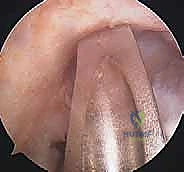

تقنيات جراحة إعادة بناء الرباط الصليبي الأمامي وأنواع الطعوم

لا يمكن خياطة الرباط الصليبي الأمامي المتمزق (إلا في حالات نادرة جداً لتمزقات معينة عند نقطة الاتصال العظمي). لذلك، يجب "إعادة بناء" (Reconstruction) الرباط باستخدام نسيج بديل يُسمى "الطعم" (Graft).

الخطوة الأولى: الفحص بالمنظار الجراحي 4K

يستخدم الدكتور